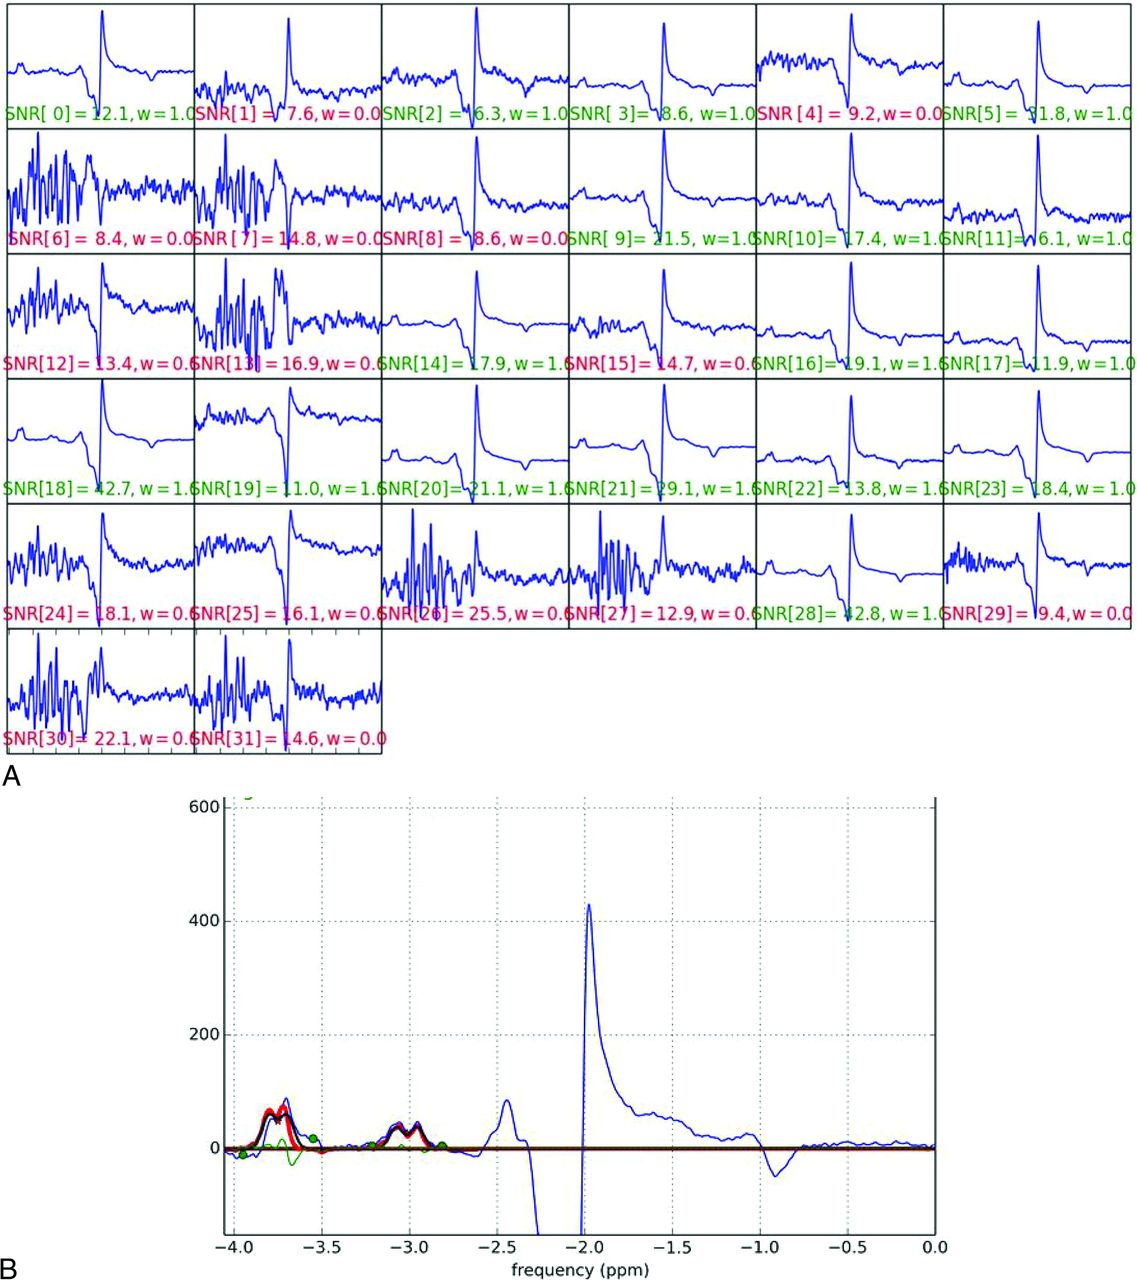

The raw GABA MR spectroscopy data were transferred to an off-line computer and processed using home-programmed MR spectroscopy analysis software, which was programmed in Python (https://www.python.org/). Raw data were averaged in the time domain and baseline-corrected, and the areas under the GABA and Glx peaks at 3.01 and 3.8 ppm were measured by fitting to double and single Gaussian functions, respectively (Fig 2). The data for 1H-MR spectroscopy at TE = 135 ms were processed using LCModel 6.3 (http://www.lcmodel.com/), and the creatine peak was measured at 3.0 ppm and used as the internal reference. GABA and Glx relative to creatine were quantified, and the GABA-to-creatine ratio (GABA/Cr) and the Glx-to-creatine ratio (Glx/Cr) were obtained. The GABA-to-Glx ratio (GABA/Glx) was also obtained.

Acquisition and spectral fitting of MEGA-PRESS MR spectroscopy. A, MR imaging data are acquired with a 3T MR imaging scanner with a 32-channel phased array head coil. The signal-to-noise ratio acquired on each channel is visually checked, and raw data with a low signal-to-noise ratio (red characters) are removed from averaging. B, Selected raw data are averaged in the time domain and baseline-corrected, and the areas under the GABA and Glx peaks at 3.01 and 3.8 ppm (red lines) are measured by fitting to double and single Gaussian functions, respectively.